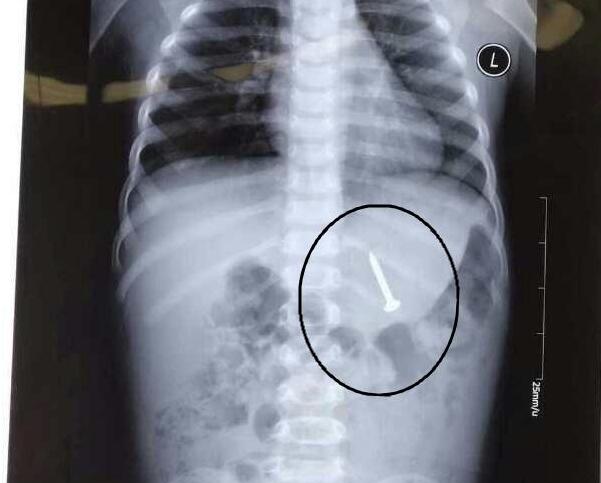

10月8日晚,聊城一名两岁半的男童在家中玩耍时,不慎将一枚长达3.3厘米的钢钉吞入肚子。锋利的钢钉在胃、肠间游走,若不及时取出,很有可能会危及生命。

聊城市人民院消化内科副主任医师焉鹏告诉记者,8日晚9点左右,家长带着孩子匆匆赶到医院求救,称孩子误吞钢钉。在对孩子进行初步检查后发现,这枚钢钉已经卡在了十二指肠较深的位置,由于钢钉长度较长,若不及时取出,很有可能造成肠道穿孔,后果不堪设想。

9日早晨5:30分,市医院的医生对孩子实施了微创手术,经过半个小时的努力,成功将钢钉取出。经过实际测量发现,这枚钢钉的长度达到了3.3厘米。